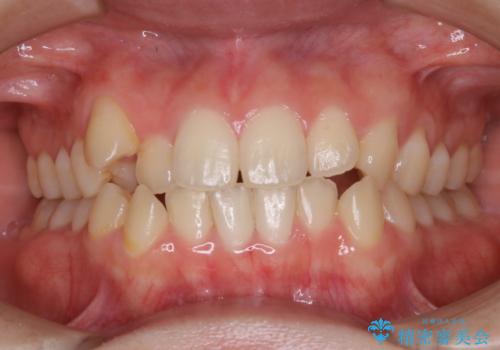

前歯のガタつきを治したい 翼状捻転マウスピース矯正